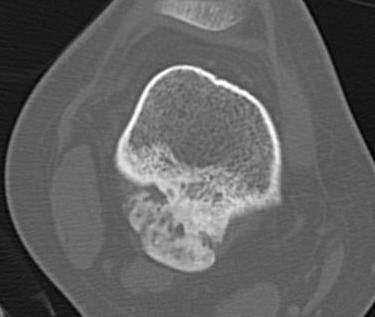

CT

Can be used to differentiate from osteochondroma

1. Parosteal OS

- attached to cortex growing into soft tissue

- normal cortex intact

2. Osteochondroma

- cortex of bone becomes cortex of osteochondroma

- medullary canal confluent with osteochondroma

- posterior femur rare